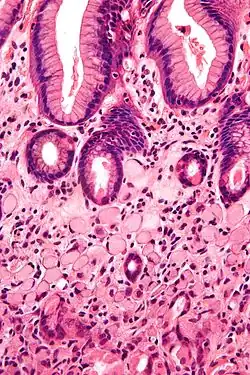

Histopatologia

Gruczolakorak jest najczęstszym nowotworem złośliwym żołądka i stanowi 90–95% wszystkich nowotworów złośliwych żołądka u ludzi[14][79][80]. Chłoniaki żołądka są drugim pod względem częstości występowania typem nowotworu złośliwego żołądka i stanowią 3–5% nowotworów złośliwych żołądka u ludzi[81][82]. Najczęstszymi chłoniakami żołądka są chłoniak typu MALT i chłoniak rozlany z dużych komórek B (DLBCL)[83], razem stanowią około 90% wszystkich chłoniaków żołądka u ludzi[82]. Pozostałe nowotwory złośliwe stanowią rzadsze złośliwe nowotwory nabłonkowe, guzy stromalne (GIST) i rakowiaki[84].

Istnieje kilka różnych klasyfikacji raka żołądka pod względem histopatologicznym. Największe znaczenie ma klasyfikacja WHO i Lauréna. Klasyfikacja WHO wyróżnia wiele różnych typów nowotworów nabłonkowych, ale dominującymi typami są rak brodawkowaty, cewkowy, śluzowy i rak o słabej kohezji[85]. Klasyfikacja Lauréna uwzględnia dwa główne typy: typ jelitowy i rozlany. Rak żołądka jest również klasyfikowany pod względem głębokości nacieku (rak wczesny i zaawansowany)[86] i typu makroskopowego[87].

Makroskopowo zaawansowany rak żołądka może przybierać formę polipowatą, grzybiastą, wrzodziejącą lub rozlanie naciekającą (tzw. linitis plastica). Postać wrzodziejąca częściej pojawia się w okolicy przedodźwiernikowej i krzywiźnie mniejszej, klasycznie w odróżnieniu od wrzodów trawiennych wykazuje bardziej nieregularne brzegi z wzniesionymi, walcowatymi krawędziami, często zawiera obszary krwotoczne i martwicy[89]. Forma polipowata częściej pojawia się w trzonie żołądka w obrębie krawędzi większej. Forma rozlanie naciekająca jest niewyraźnie ograniczonym guzem o owrzodziałej powierzchni zwężającym światło żołądka. Na przekroju zaawansowany rak jest szarobiałą lub żółtobiałą masą o spoistej do twardej konsystencji i zawiera obszary krwotoków i martwicy[90]. Mikroskopowo składa się z cewkowych, groniastych lub brodawkowatych struktur lub słabo spoistych pojedynczych komórek, które naciekają głębsze warstwy ściany żołądka[91]. Komórki nowotworowe mogą posiadać cechy komórek typu jelitowego, również wykazując różnicowanie w kierunku komórek okładzinowych, argyrofilnych komórek endokrynnych oraz komórek Panetha. Komórki zwykle produkują śluz, często stwierdza się podwyższone stężenie CEA i Ca 19-9[92].